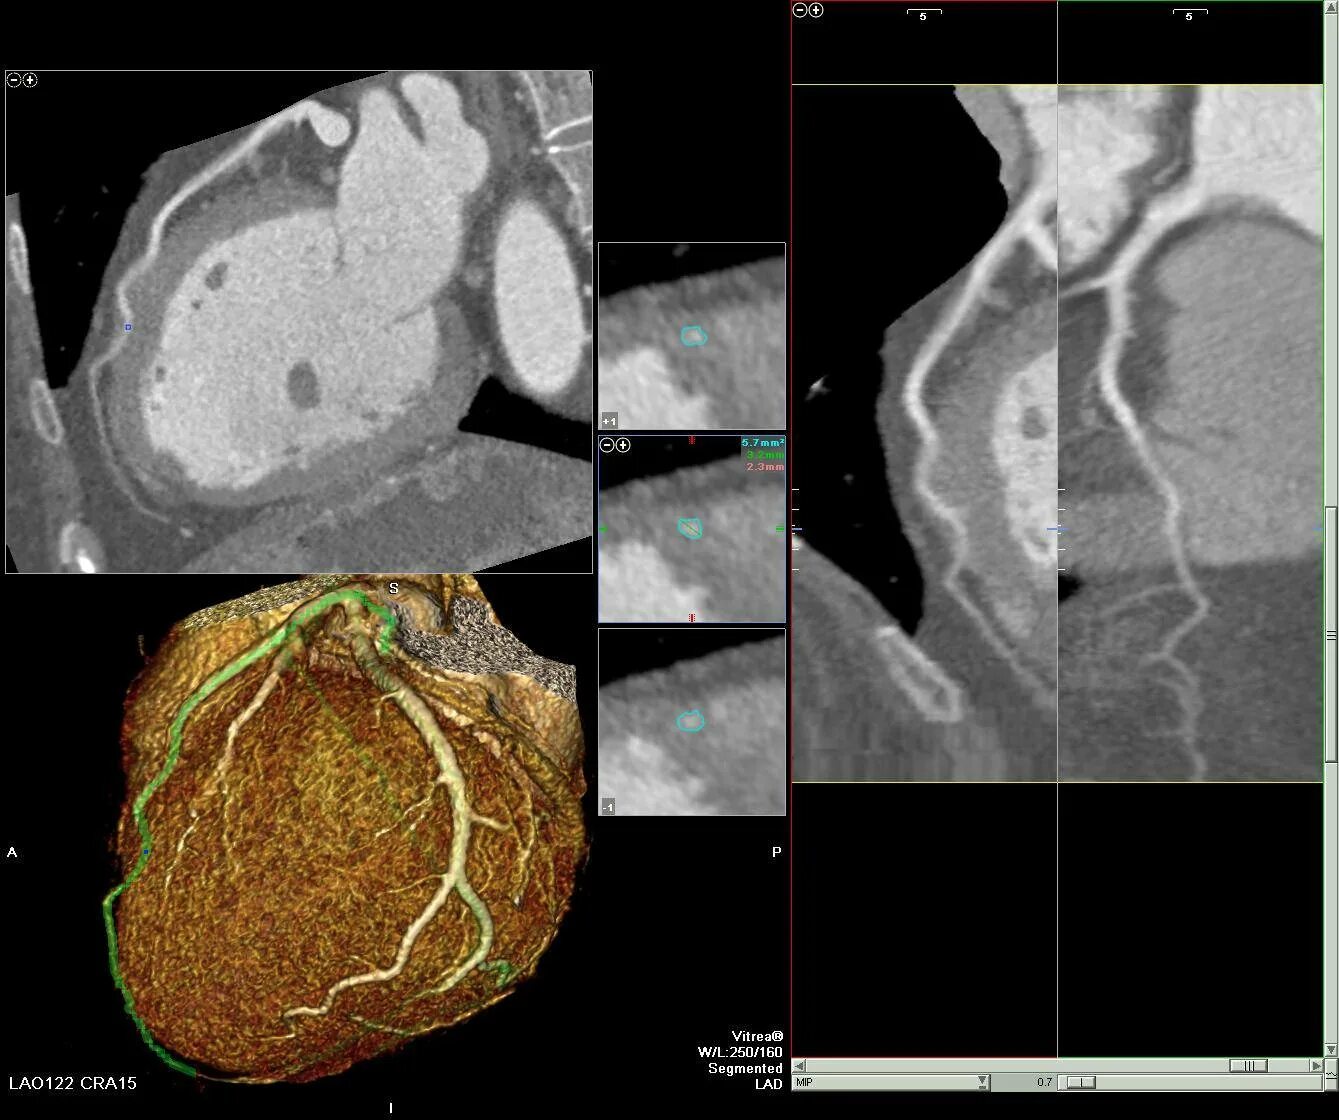

Как делают кт сердца